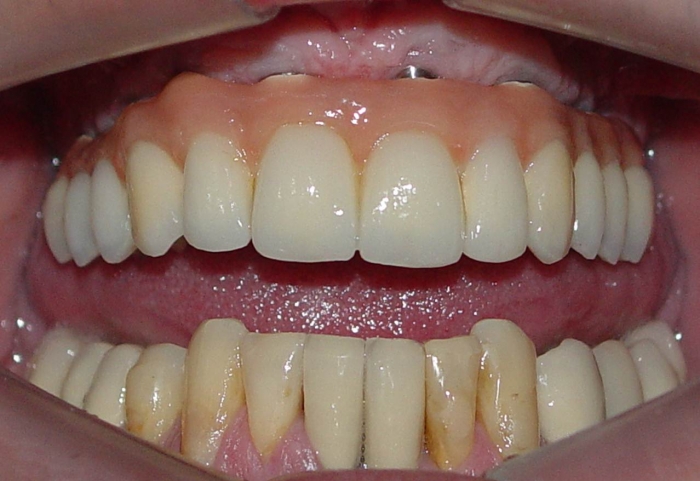

Prótese fixa em porcelana superior

Sorriso do caso terminado em abril de 2012